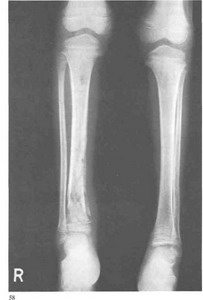

Хотя распознавание ясно на основании типичных клинических данных, рентгенологическое исследование вносит уточнение и является ценным диагностическим подспорьем. Всегда необходимо рентгенологически, хотя бы даже рентгеноскопически, проверить весь скелет в целом, чтобы не просмотреть фиброзную дисплазию костей. Рентгенограммы черепа показывают значительные односторонние костные разрастания главным образом верхней и нижней челюстей, скуловой, носовой и других костей лицевого черепа. Разрастания имеют обычно диффузно-склеротический и гиперостотичеокий характер. При переходе процесса на мозговой череп, на лобную кость, он обычно перекидывается и на другую сторону лица, и при этом асимметрия остается. Черепные швы составляют некоторый барьер для костных разрастаний, перед швами рост и распространение патологического процесса подчас задерживаются или даже полностью обрываются.

Диференциально-диагностически важно, что придаточные полости носа замещаются костной тканью, их воздушность теряется, чего не бывает при обезображивающей и паратиреоидной остеодистрофии. Ряд сложных клинических неврологических симптомов получает благодаря дополнительному уточненному рентгенологическому исследованию свое объяснение в костном сужении отверстий или каналов для того или иного нервного ствола. Каждый случай этого своеобразного хронического заболевания носит в себе неповторяемые индивидуальные особенности.